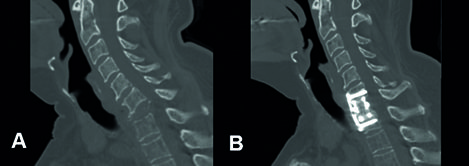

Corpectomie

In sommige gevallen haalt de chirurg ook het aangetaste wervellichaam aan de voorzijde van het ruggenmerg weg. De chirurg vervangt deze door een kunstwervel, een type ‘cage’. De chirurg kan deze uitdraaien, zodat deze steunt op het boven- en onderliggende wervellichaam.

- Na drie maanden bezoekt u de polikliniek voor een controle. We maken een afspraak om een röntgenfoto en/of een CT-scan te laten maken. Hierop kan de arts zien of de wervels goed zijn vastgegroeid. Draagt u een korset of halskraag? Dan vertelt de neurochirurg wanneer u deze niet meer hoeft te dragen.